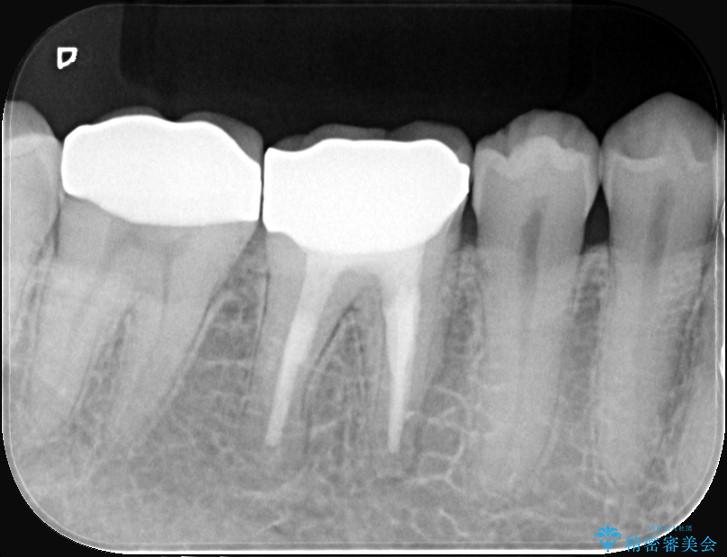

診査の結果、古い銀歯の隙間から新しい虫歯が広がっていました。ここは噛む力が強くかかる場所のため、このまま詰め物で治すと、部分的な詰め物では残存している自分の歯に負担が集中し、将来的に歯が割れてしまう「歯冠破折」のリスクが高い状態でした。

虫歯を丁寧に除去し、審美性・耐久性に優れたセラミッククラウンにやり替える治療計画を立案しました。